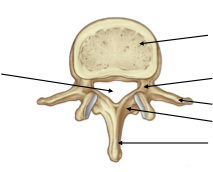

Label the image

Top to bottom (Right):

1) vertebral body

2) pedicle

3) transverse process

4) Lamina

5) Spinous process

Left:

Vertebral canal

What forms the neural arch?

Pedicle, transverse process, lamina, spinous process